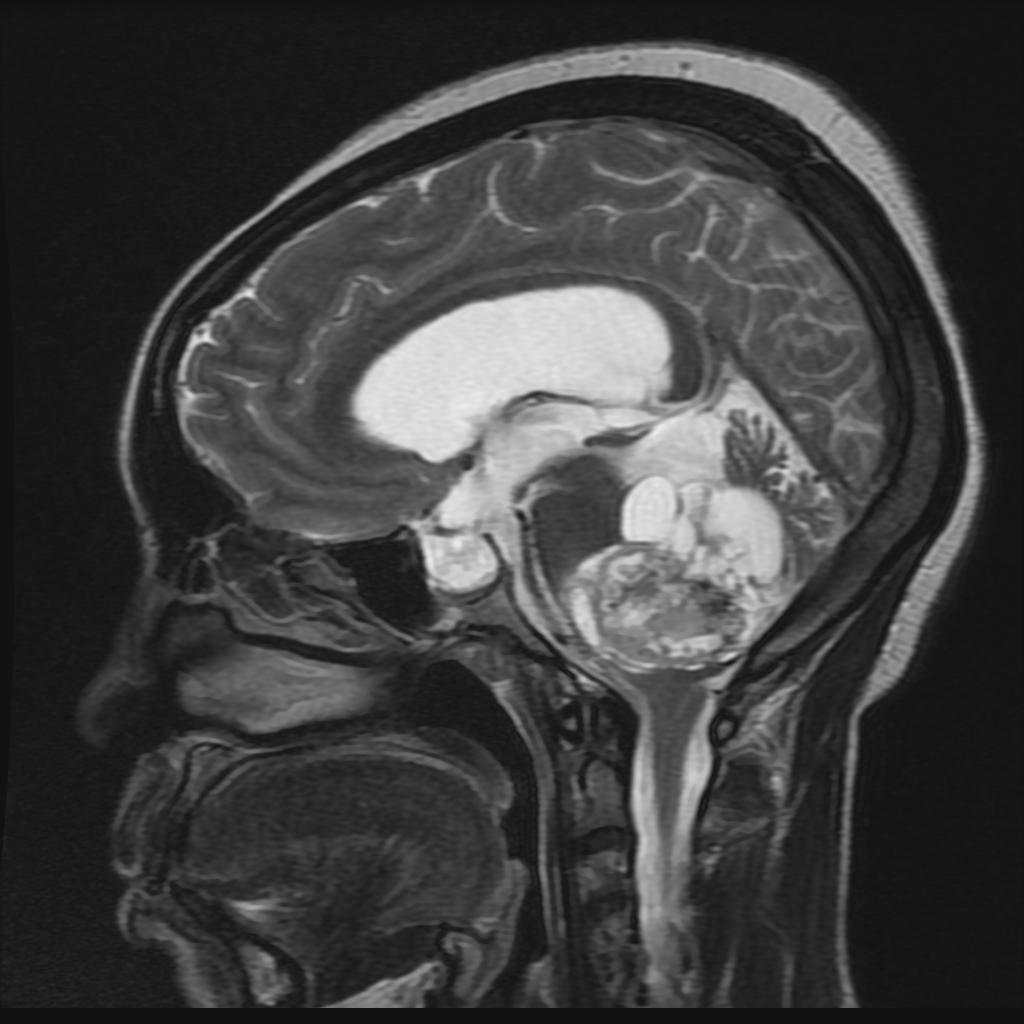

МРТ головного мозга: показания и результаты

Раздел: Визуальный дайджест